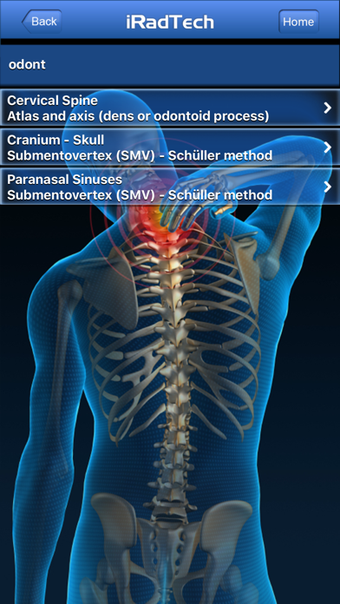

IRadTechهو برنامج إصدار كامل لأجهزة iPhone ، وهو جزء من فئة "الطب" أ>.

حول IRadTech لأجهزة iPhone